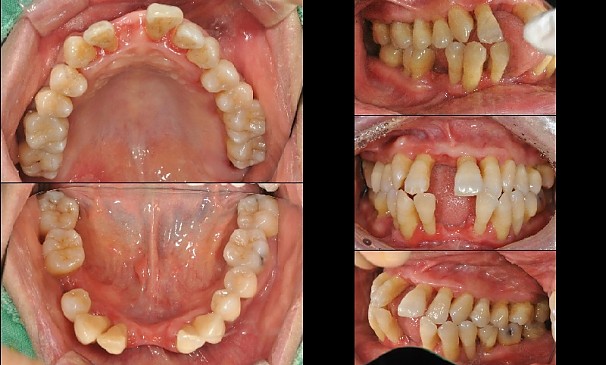

명OO님 전후사진 | 치료 기간 : 30

치료 후